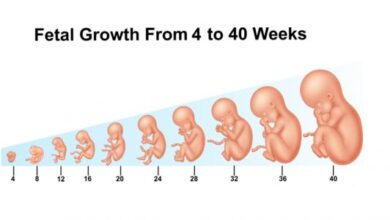

يمر الجنين بمراحل عدة من النمو خلال أشهر الحمل التسعة، وتتطور خلال هذه المراحل أنواع الحركة، وفي التالي بيان لأهم ما يمر به الجنين في هذه الأشهر:[٧][٨]

- الشهر الأول: حيث تنمو البويضة المخصبة، ويحيط بها كيس مملوء بسائل أمنيوسي (بالإنجليزية: Amniotic Sac)، والذي يعمل على حماية البويضة أثناء تطورها. كما تبدأ المشيمة بالتطور، لإمداد الجنين بالتغذية اللازمة. ومع نهاية الشهر الأول، يتكون القلب بشكله البدائي، ويبدأ بالنبض بمعدل 65 نبضة في الدقيقة الواحدة.

- الشهر الثاني: حيث تبدأ معالم وجه الجنين بالتكوّن بشكل أوضح، وتبدأ البراعم التي ستنمو لتشكل أطراف الجنين بالظهور بشكل تدريجي، كما يكون حجم الرأس كبير نسبة لحجم الجسم خلال هذا الشهر. ويبدأ الجهاز العصبي، والهضمي، والعظمي بالتطور خلال هذا الشهر.

- الشهر الثالث: حيث تتطور الأطراف خلال هذا الشهر بشكل كامل، وفي نهاية هذا الشهر تكون أعضاء الجسم جميعها ظاهرة، مع العلم بأنّها ستستمر بالتطوّر والنضج خلال الأشهر القادمة. كما أنّ فرص خسارة الحمل تقل بشكل ملحوظ بعد الشهر الثالث منه.

- الشهر الرابع: أهم ما يحدث في هذا الشهر أنّ الجهاز العصبي الخاص بالجنين يبدأ بالعمل، كما يمكن للطبيب أن يقوم بسماع نبضات قلب الجنين عبر أجهزة خاصة.

- الشهر الخامس: وهو الشهر الذي يبدأ فيه الجنين بالحركة الملحوظة من قبل الأم، ويبدأ شعره بالنمو.

- الشهر السادس: حيث تنفصل جفون العينين عن بعضها البعض، ويتمكّن الجنين من فتح عينيه، كما يستجيب للأصوات الخارجية بالحركة أو زيادة معدل نبض القلب. وتجر الإشارة إلى أنّ فرصة نجاة الجنين تحت العناية المركزة في حال الولادة المبكرة خلال هذا الشهر تُعتبر جيدة في حال حصل ذلك بعد الأسبوع 23 من الحمل.

- الشهر السابع: يستمر الجنين خلال هذا الشهر بالنمو وتخزين الدهون في جسمه، كما يكتمل تطور حاسة السمع لديه بشكل كامل، ويبدأ السائل الأمنيوني بالاضمحلال تدريجياً.

- الشهر الثامن: وهو الشهر الذي يشهد فيه الدماغ تطوراً سريعاً، وتزداد فيه الحركة بشكل ملحوظ. كما تُعتبر جميع أعضاء الجسم عدا الرئتين كاملة النمو.

- الشهر التاسع: يكتمل في هذا الشهر تطور ردات فعل الجنين وتناسقها، كالرمش، وحركات الرأس، واليدين. ويكتمل خلاله نمو الرئتين تقريباً، ومن الطبيعي أن تقل حركة الجنين خلال هذا الشهر نظراً لضيق المساحة. كما يستعد الجنين لمرحلة الولادة عن طريق تغيير موضعه داخل الرحم، ليصبح رأسه متجهاً للأسفل، وتموضعه في أسفل الحوض. ويبلغ وزن الجنين في نهاية هذا الشهر قرابة الثلاثة كيلوغرامات، ليصبح الجنين مستعداً للخروج إلى العالم الخارجي.